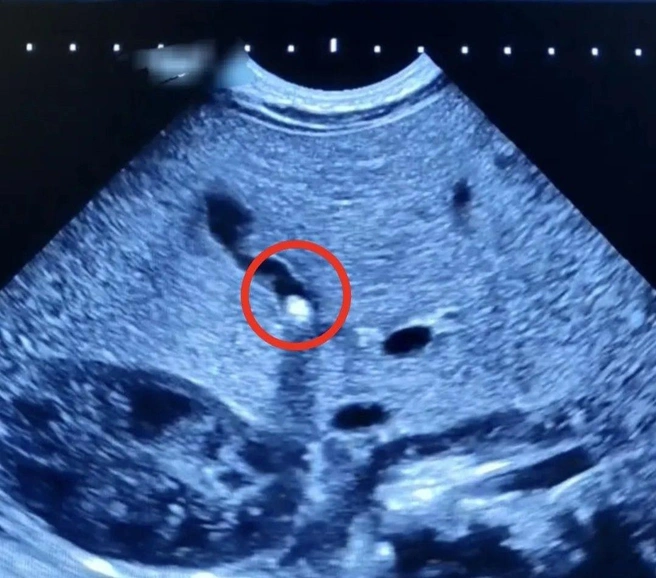

Мать малыша обратилась в больницу с жалобой на плохую прибавку в весе и желтушное окрашивание кожи и склер. Ультразвуковое исследование брюшной полости выявило камень небольшого размера, частично перекрывавший желчный проток.